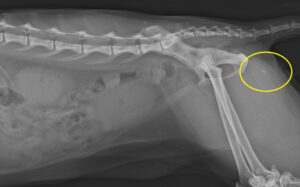

2年前の膀胱結石と尿道結石 2度に分けて手術